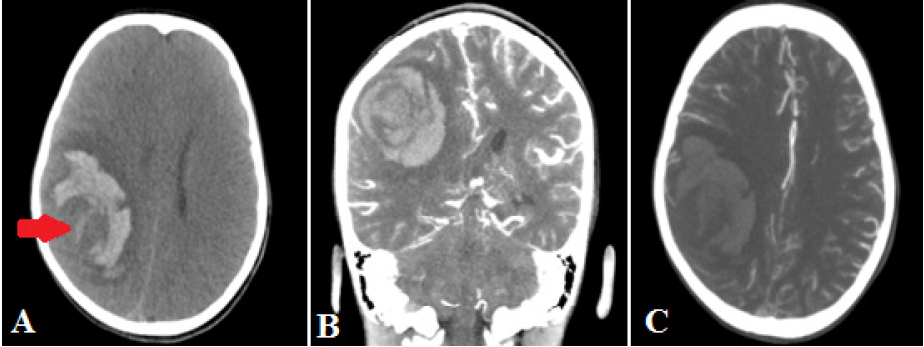

Paciente varón de 5 años ingresó a emergencia en octubre del 2020 por presentar irritabilidad, trastorno del sensorio progresivo, náuseas y vómitos en 3 oportunidades tras caída de cama. Al examen físico, el paciente presentaba un puntaje en la Escala de Coma de Glasgow (ECG) de 11, con pupilas isocóricas, fotorreactivas y hemiparesia izquierda. La tomografía cerebral sin contraste evidenció hemorragia intraparenquimal en la región fronto-parietal derecha de aspecto reciente con edema vasogénico con imagen de aspecto nodular en su interior; asimismo, la angiotomografía cerebral no mostraba malformación arteriovenosa asociada (figura 1). El paciente ingresó a la Unidad de Cuidados Intensivos Pediátricos, donde fue intubado y recibió medicación para neuroprotección. Ante condición clínica del paciente, se decidió realizar una intervención quirúrgica de emergencia para evacuación del hematoma intraparenquimal. Tras la craneotomía y apertura de la duramadre se evidenció una aparente lesión tumoral infiltrativa, cortico-subcortical sangrante con plano de clivaje parcialmente definido asociado a hematoma intraparenquimal. Se realizó una resección quirúrgica amplia de la lesión. No hubo complicaciones durante el intraoperatorio. El paciente cursó febril en el día 1 del postoperatorio. La tomografía cerebral sin contraste de control, en el día 2 del postoperatorio, no evidenció sangrado en el lecho operatorio de necesidad quirúrgica. Sin embargo, el paciente presentó ese día de manera súbita paro cardiorrespiratorio, falleciendo a pesar de las maniobras de reanimación. La muestra tumoral fue informada como sarcoma cerebral no diferenciado con inmunohistoquímica: vimentina positiva, receptor de progesterona negativo, EMA negativo, desmina negativo, actina negativa, CD99 negativo, GFAP negativo, p53 positivo, ki67 90%.

A: corte axial de tomografía cerebral sin contraste muestra hemorragia fronto-parietal derecha con imagen nodular en su interior (flecha roja), con desplazamiento de línea media y colapso de ventrículo lateral derecho. B: corte coronal de tomografía cerebral muestra hemorragia sin captación anormal de contraste. C: corte axial de angiotomografía cerebral no muestra malformación arteriovenosa asociada.